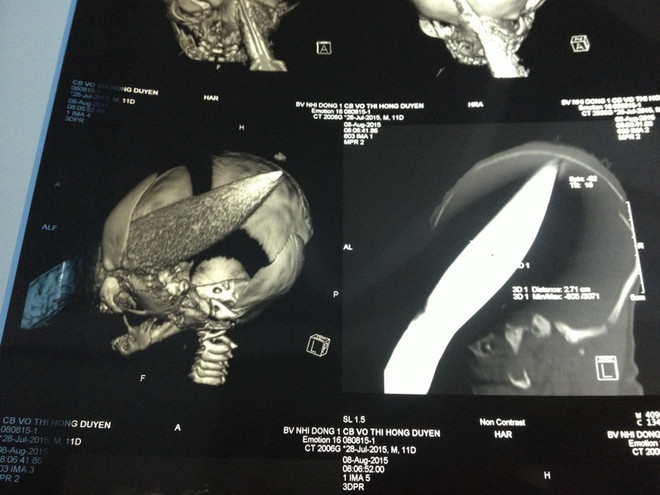

Cứu bé trai 11 ngày tuổi bị người phụ nữ đâm dao xuyên qua sọ ảnh 1Hình ảnh chụp X-quang. (Ảnh do bệnh viện Nhi đồng 1 cung cấp)

Ngay sau đó, bệnh viện tiến hành truyền dịch, chụp X-quang, CT scan để đánh giá các tổn thương. Kết quả CT scan cho thấy, lưỡi dao dài 10cm đâm từ hốc mắt bên trái xuyên qua sọ não kéo dài đến đỉnh sọ bên phải và có thể nhìn thấy phần lưỡi dao đâm ló ra bên ngoài.

Con dao đã đâm xuyên qua sọ não, làm vỡ xương trán, gây tổn thương vùng hạ đồi não. May mắn là mắt trái không bị tổn thương, phản xạ đồng tử bình thường.

Để thực hiện ca phẫu thuật, các bác sỹ đã lật vùng da trán lên sau đó khoan cắt một mảng sọ não dài khoảng 6cm để phơi bày vết thương. Sau khoảng 3 giờ phẫu thuật, con dao được lấy ra thành công. Con dao được lấy ra khỏi đầu cháu bé là một loại dao bầu, dài 28cm, ngang 2,7cm.